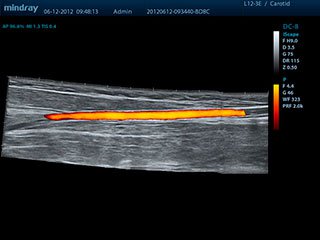

УЗИ сосудов

Благодаря полному набору специализированных датчиков и предустановок, аппарат Mindray DC-8 позволяет провести профессиональную диагностику сосудистой системы.